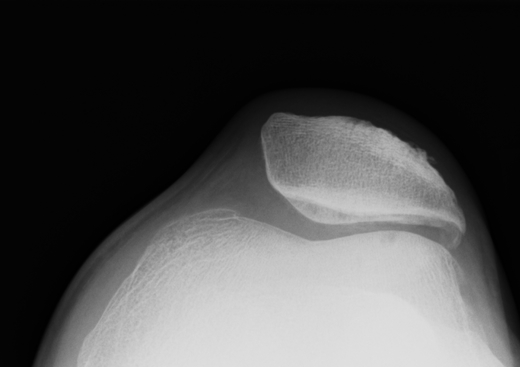

X-ray

Narrowing / osteophytes / sclerosis

Tilt / subluxation

Tilt Subluxation / osteophytes